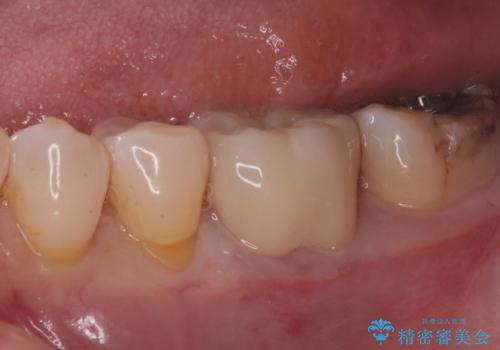

白い被せ物が入り、とても満足して頂けました。

現在銀の詰め物、被せ物のやりかえを検討しているそうです。